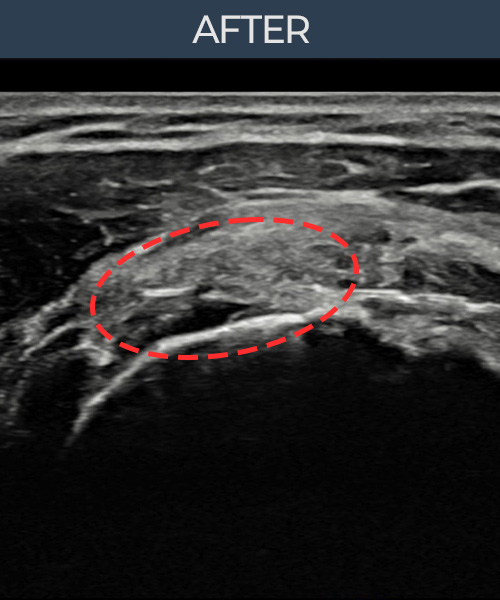

정ㅇㅇ님 · 좌측 극상근건 부착부 부분파열

좌측 어깨 부착부 부분파열로 팔을 들어 올릴 때마다 통증이 심해 내원하셨습니다. 초음파 검사에서 극상근건 부착부 에코 단절이 확인되었으며, 어깨인대 축소봉합술 후 힘줄 부착부 연속성이 완전히 회복되었습니다.